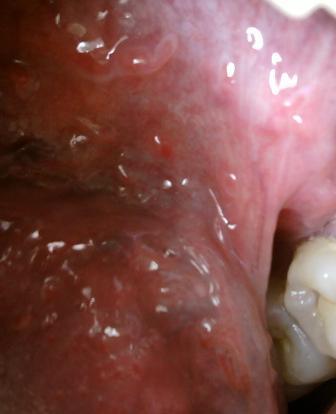

石家庄九州皮肤病医院 > 尖锐湿疣 > > > 孕妇患上尖锐湿疣应该怎么办尖锐湿疣是现在多发的性病,并且这种疾病传染性是比较强的,其中母婴传染就是其中一种。当孕妇患上尖锐湿疣之后,应该谨慎,如果在早期发现患病,一般临床上医生是建议最好终止妊娠。如果是不想放弃,那么最好是采取必要的措施控制病情,建议选择破腹产生产方式,这样以避免病毒通过产道传染给新生儿。